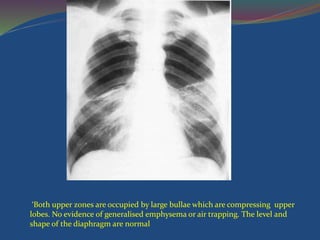

‘Both upper zones are occupied by large bullae which are compressing upper

lobes. No evidence of generalised emphysema or air trapping. The level and

shape of the diaphragm are normal

‘Both upper zonesare occupied by large bullae which are compressing upper lobes. No evidence of generalised emphysema or air trapping. The level and shape of the diaphragm are normal